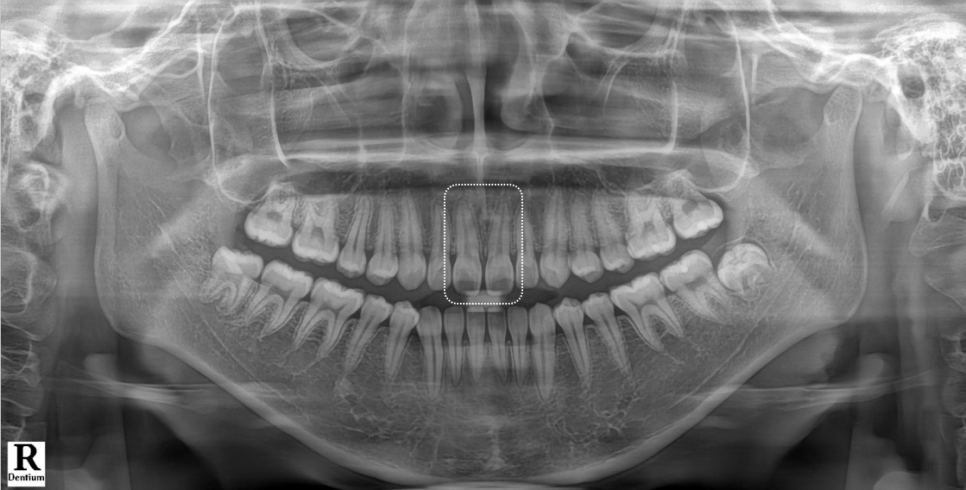

촬영 : 251030

엑스레이를 보면, 뿌리는 벌어지지 않고 정상적인 위치에 있었는데요.